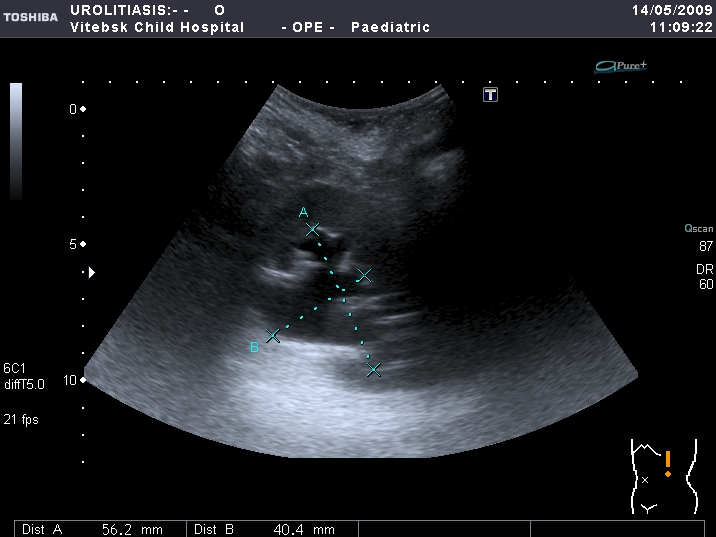

Мочеточники в нижней трети

Если честно, и я изначально не совсем понял, где находится конкремент (а это конечно же конкремент), локализованный на урограммах. При первичном исследовании на УЗИ его я не видел (либо он спрятался за тенью конкремента мочевого пузыря, либо я обрадовался редкой находке конкремента такого размера в мочевом пузыре - 2.5 см, и не посмотрел что ниже). Тем не менее при ретроспективном анализе архивированных сонограмм, как мне кажется, он попал в один из сканов, м.б. не совсем чётко.

I20111114160229796.jpg

И всё -же, где конкремент :?: